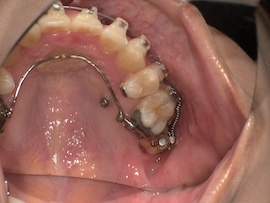

そして1ヶ月後、

左上の親知らずとその手前の歯の間に隙間があり、今は食事のたびにものが詰まります。

その隙間を閉じつつ左側の噛み合わせをより良くするため、再度ゴムかけをすることになりました。

写真にはないですが今回は左上の3番目(犬歯)と左下の7番目(一番奥)にゴムをかけます。以前左下は6番目でゴムかけをしていたのでさらにかけるのが難しくなりましたが、それでもやはりすぐに慣れるものです。